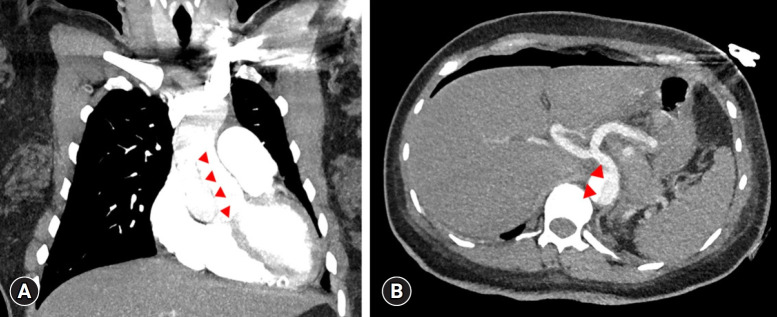

Aortic dissection in pregnant patients results in an inpatient mortality rate of 8.6%. Owing to the pronounced mortality rate and speed at which aortic dissections progress, efficient early detection methods are crucial. Here, we highlight the importance of early chest computed tomography (CT) for differentiating aortic dissection from pulmonary embolism in pregnant patients with dyspnea. We present the unique case of a 38-year-old pregnant woman with elevated D-dimer and N-terminal pro-brain natriuretic peptide (NT-proBNP) levels, initially suspected of having a pulmonary embolism. Initial transthoracic echocardiography did not indicate aortic dissection. Surprisingly, after an emergency cesarean section, a chest CT scan revealed a DeBakey type I aortic dissection, indicating a diagnostic error. Our findings emphasize the need for early chest CT in pregnant patients with dyspnea and elevated D-dimer and NT-proBNP levels. This case report highlights the critical importance of considering both aortic dissection and pulmonary embolism in the differential diagnosis of such cases, which will inform future clinical practice.

Abstract Image